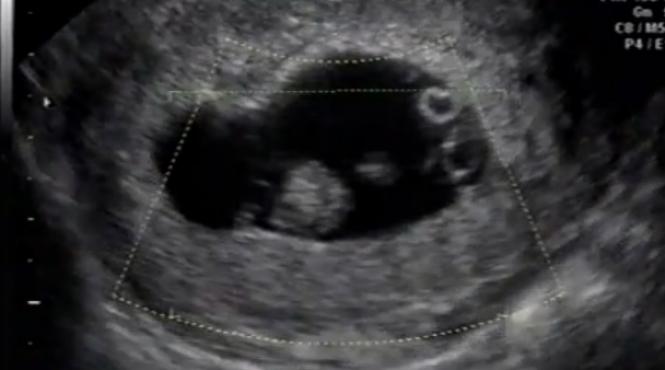

Ştiri despre O Dată La 100 De Milioane De Naşteri